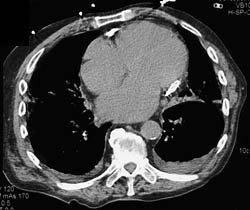

Diagnosis

Enlarged Right Atrium and Pe